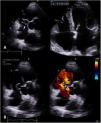

At the first evaluation, the patient was asymptomatic and maintained regular physical activity (used to run 10 km twice a week). The physical examination was unremarkable except for a slight continuous heart murmur. Transthoracic and transesophageal echocardiogram confirmed the existence of an aorto-atrial fistula with left to right cardiac shunt, caused by a rupture SOVA (Figure 1A and B; videos 1–4) with dilatation of the right heart chambers (Figure 1C).